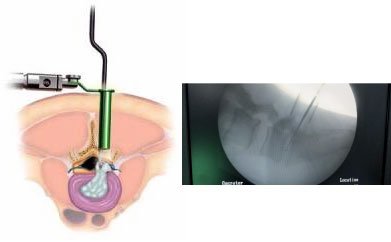

Endoscopic Spine Surgery

Stichless Spine Surgery

Incision as small 2cm

Faster Recovery